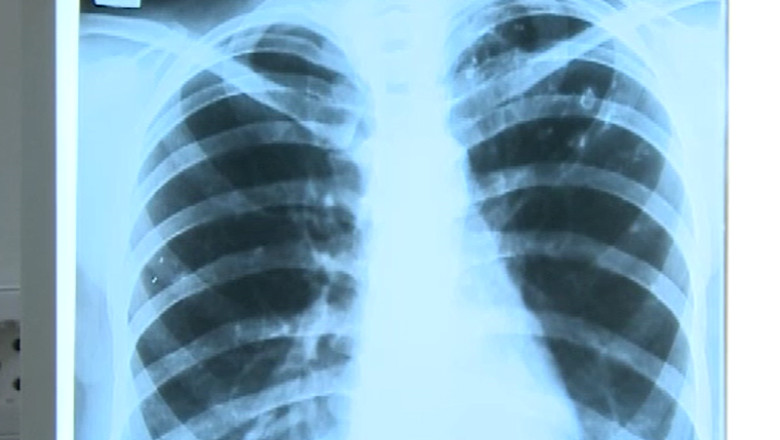

Tuberculoza poate fi vindecată, dacă e depistată la timp, iar bolnavul respectă cele 6 luni de tratament recomandate. De multe ori, bolnavii întrerup tratamentul, iar boala recidivează. În plus, bolnavii de tuberculoză spun că refuză să stea la izolare şi din cauza condiţiilor.

În prima jumătate a acestui an au fost înregistrate aproape 8.500 de cazuri noi de tuberculoză, ţara noastră fiind pe primul loc în Uniunea Europeană. Iaşiul este pe locul trei pe ţară, după Bucureşti şi Dolj cu 369 de bolnavi. Specialiştii atenționează însă că, de fapt, numărul lor este mai mare şi că reprezintă un pericol pentru societate.

Printre simptomele tuberculozei se numără tusea, lipsa poftei de mâncare, scăderea în greutate, oboseala şi senzația de sufocare.